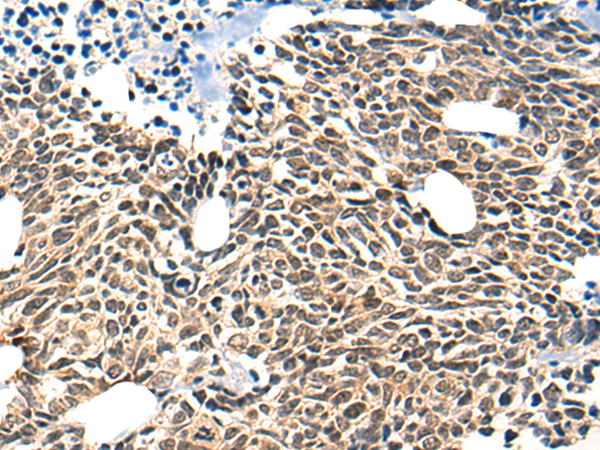

分类: 科研抗体货号: P13146别名: SCP; SPC; UCNIII应用: WB,IHC反应种属: Human